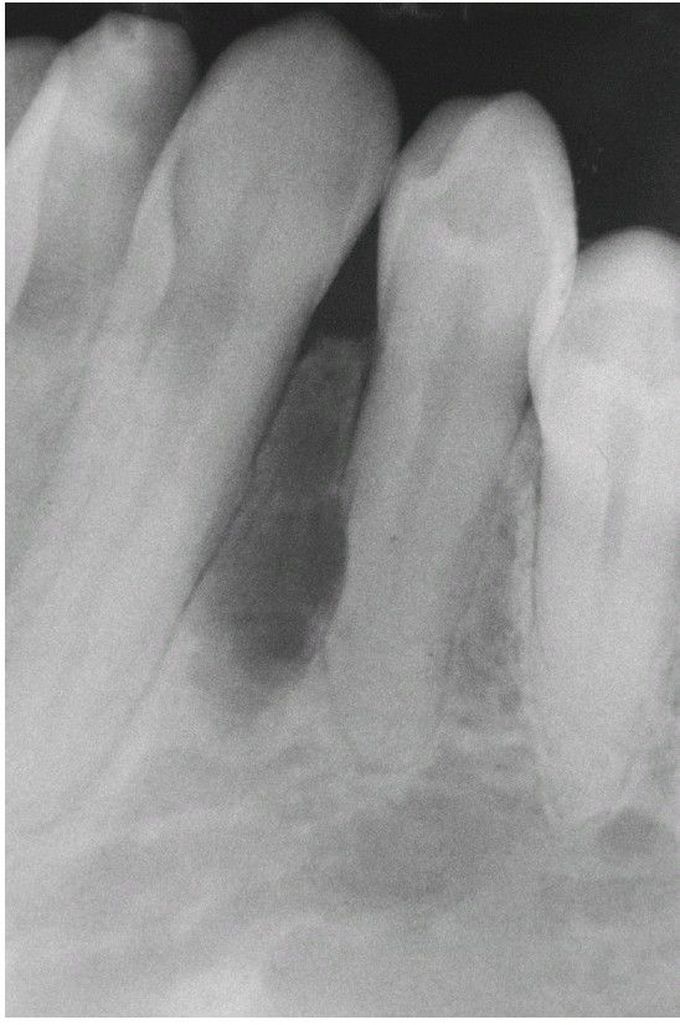

Ameloblastoma Radiograph

. This small unilocular radiolucency lesion could easily be mistaken for a lateral periodontal cyst.